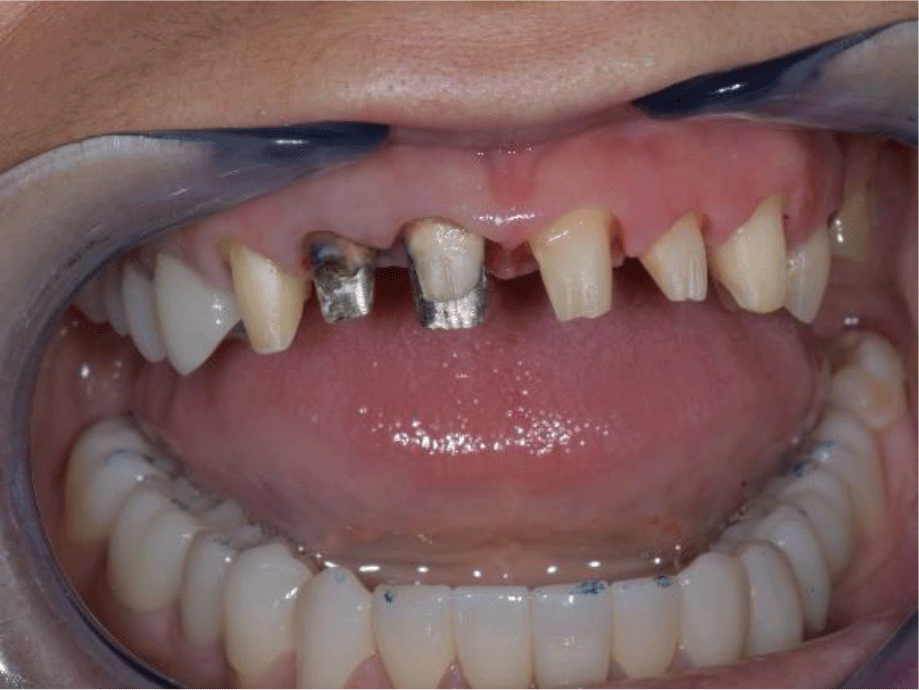

A 35-year-old female patient, Bulgarian restaurant owner, sought help due to impaired aesthetics, as a result of abraded tooth surfaces and severe symptoms of the right TMJ.

Intraoral examination of the upper jaw revealed a metal-ceramic construction on 13, 12, 11, 21, 22, 23, 24, missing 18, 16, 25, 26. The metal-ceramic construction was made 13 years ago, and was in good condition except for small fractures of the ceramic on the palatal surface and palatal staining of the gingiva by the metal base. The distal available teeth were medialized (Figures 1 and 2).

On the lower jaw, an advanced phase of abrasion (Attritio dentis cum abrasione) of the frontal teeth was established, reaching the dentin area. Defects of the dentitions were solved with ceramic restorations of 35, 36, 37 on the left and 45, 46 on the right. The occlusal plane was incorrect – the lower frontal teeth were higher. There was a deep overlap of the lower frontal teeth in central occlusion (Figures 3 and 4).

26dd931c-41d3-478d-bec1-8cb211d0a4b8_figure3.gif

Figure 3. Abraded lower teeth and occlusal plane at initial presentation.

26dd931c-41d3-478d-bec1-8cb211d0a4b8_figure4.gif

Figure 4. Central occlusion shown on initial presentation.

During palpation of the TMJ, the patient responded with mild pain on the right side.